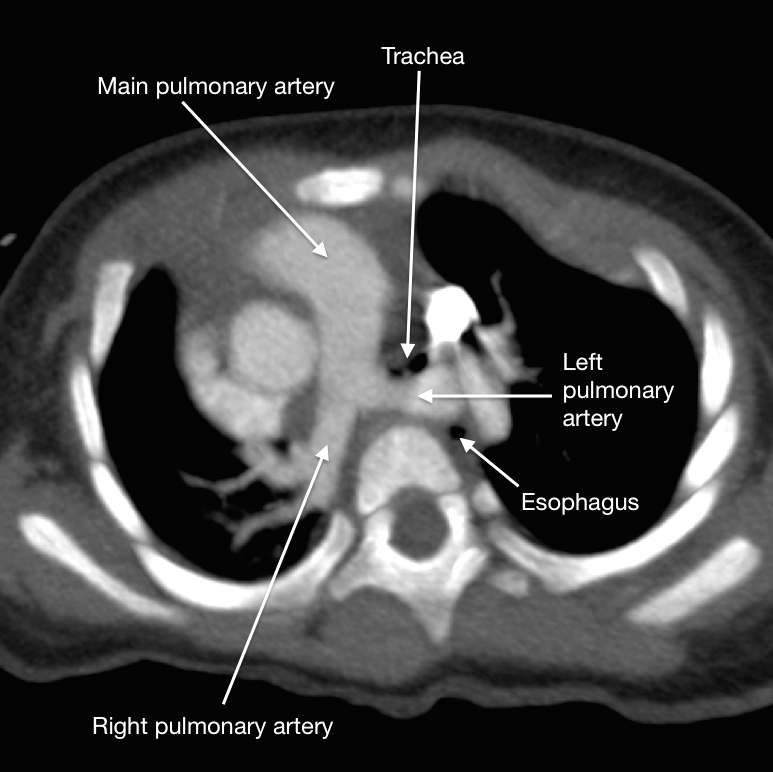

Aberrant left pulmonary artery

Aberrant left pulmonary artery, also known as pulmonary sling, represents an anatomical variant characterised by the left pulmonary artery arising from the right pulmonary artery and passing above the right main bronchus and in between the trachea and oesophagus to reach the left lung. It may lead to compression and focal stenosis of the trachea.

Aberrant left pulmonary arteries are thought to arise from a failure of formation of the 6th aortic arch. They have an anomalous origin from the posterior wall of the right pulmonary artery before coursing to the left lung passing posterior to the trachea and anterior to the oesophagus.

CT/MRI

The main bronchi have horizontal courses (i.e. low T-shaped carina), and vascular anatomy is normally well delineated on CT or MR angiography. Atelectasis may be seen in the upper lobes.

it is the only vascular ring to pass between the trachea and oesophagus

it compresses the trachea posteriorly and causes anterior impression over the oesophagus on lateral radiographs